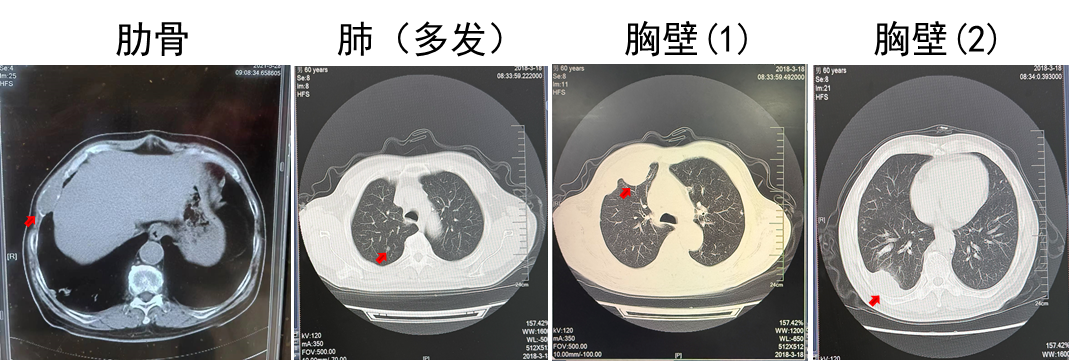

2018.03 PET-CT提示多发肺转移,肋骨转移

2018.03.22胸壁穿刺显示转移性癌,考虑肾来源

诊断为T2N0M1,IV期,IMDC低危

2018.03.22舒尼替尼50 mg QD。肋骨肿瘤注射唑来膦酸3周1次(共3次),同步放疗3 Gy(共10次)。

疗效:肋骨病灶疾病稳定(2年),肺部病灶部分缓解(2年)。

该例患者诊断为左肾透明细胞癌,T2N0M0,术后5.5年复发,伴肋骨转移、肺转移和胸壁转移。结合循证医学证据及中国临床肿瘤学会(CSCO)肾癌诊疗指南对低危患者推荐,优先使用舒尼替尼进行一线治疗,患者出现不耐受情况,调整剂量后肺部病灶获得部分缓解,肋骨病灶疾病稳定,PFS 2年。后续进展可考虑其他治疗方案。